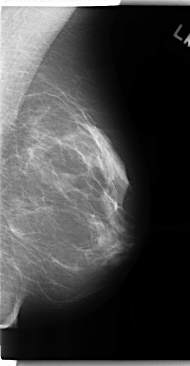

C_0149_1.RIGHT_MLO

RIGHT_MLO LINES 4712 PIXELS_PER_LINE 2488 BITS_PER_PIXEL 12 RESOLUTION 50 OVERLAY